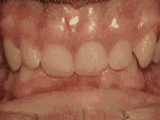

Crowding of the teeth

Patient started treatment at age eleven and wore braces for twenty-six months. He loves his new smile.